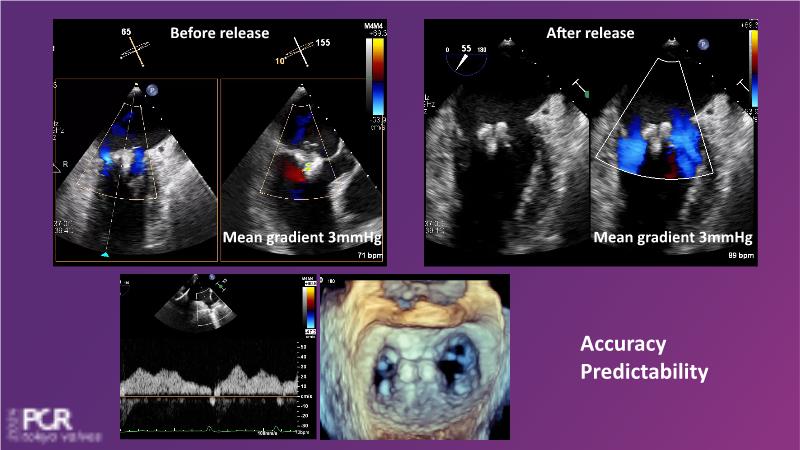

Watch this session to get an overview of a new TEER device, follow the step-by-step procedure related to initial experiences with this device for a Japanese patient with degenerative mitral regurgitation, learn about the latest data from RCT and registries, and follow discussions of challenging TEER cases!

- To understand how novel TEER device provides new possibilities in TEER

- To learn procedural step-by-step of novel device